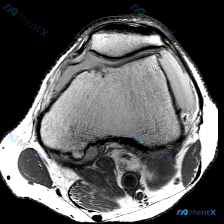

这份病例提供的是膝关节MRI轴位影像,核心观察结果如下:

- 髌股关节:关节间隙清晰,但髌骨外侧关节面和对应股骨滑车外侧面的软骨存在信号不连续、变薄、表面毛糙,髌骨软骨下骨表面信号不均匀、轮廓改变,提示软骨异常;关节周围没有明显滑膜增生或大量积液

- 骨骼结构:股骨髁形态完整,皮质连续,没有明显骨髓水肿、骨挫伤表现

- 周围软组织:髌骨支持带连续性完整,关节周围软组织没有明显炎性渗出或占位

最突出的异常就是髌股关节面的改变:髌骨软骨下骨和软骨交界处信号不均匀,软骨面不平整,对应的股骨滑车关节面也有类似的软骨信号异常,符合软骨退变或磨损的表现。